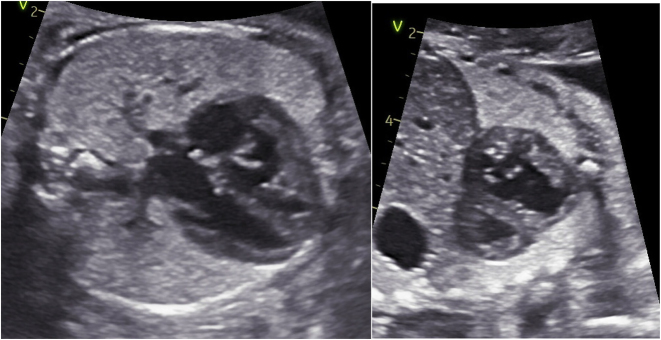

Case presentation: We describe a monochorionic diamniotic pregnancy complicated by twin anemia polycythemia sequence wherein the recipient twin developed signs of right heart failure secondary to premature ductus arteriosus constriction, requiring iatrogenic preterm delivery to avoid intrauterine demise.

Abstract Image